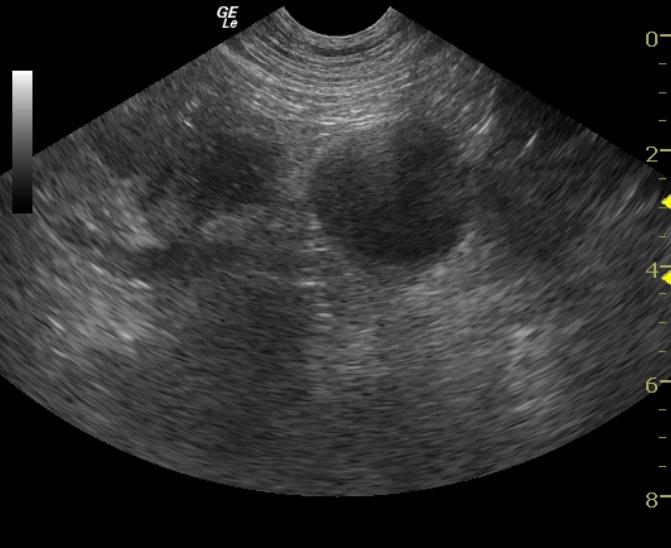

A 5-year-old FS Boxer dog was presented for vomiting, diarrhea, anorexia, and weight loss. The blood chemistry revealed elevated ALT and elevated AST enzyme activities. The CBC showed a leukocytosis consisting of a neutrophilia and a monocytosis. Thoracic radiographs were performed and there was no evidence of mass lesions and the cardiac silhouette was within normal limits.